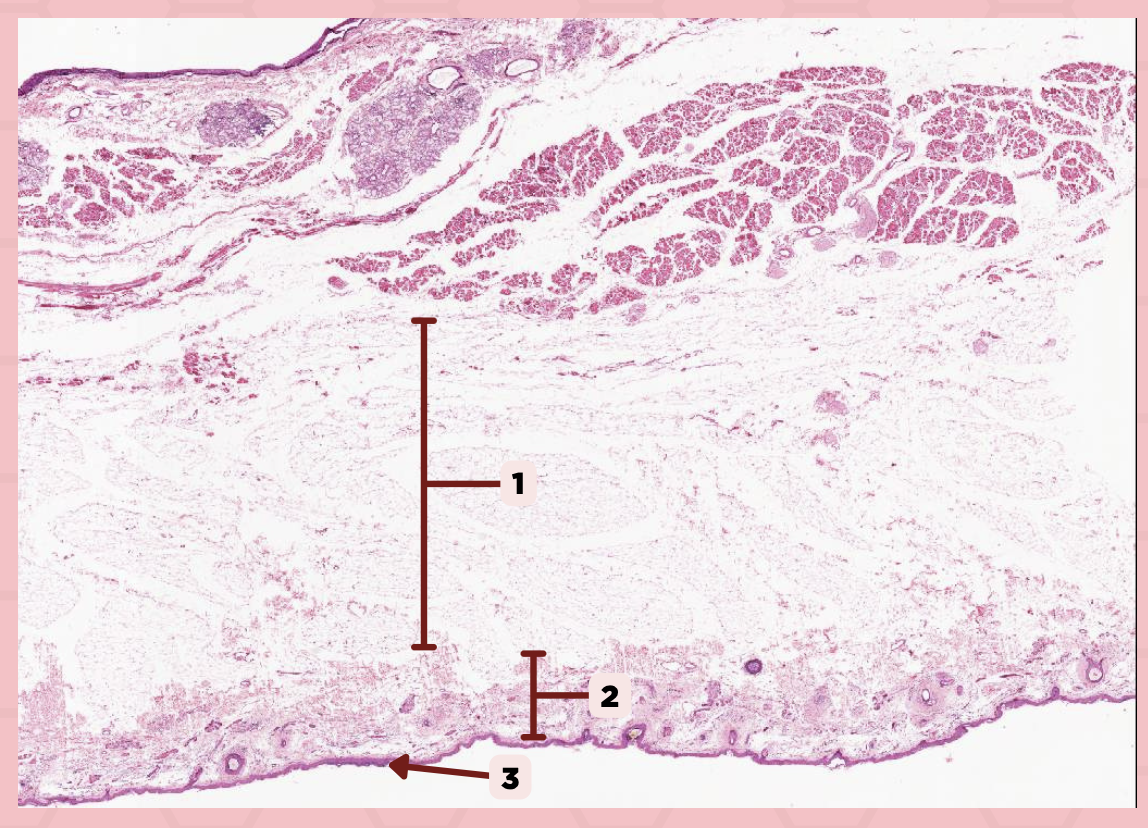

Cheek (Coronal Section)

Identify the specimen.

Hypodermis

Identify the structure labeled as 1.

Dermis

Identify the structure labeled as 2.

Epidermis

Identify the structure labeled as 3.

a. Keratinized stratified squamous epithelium

What is the lining of the structure labeled as #1?

a. Keratinized stratified squamous epithelium

b. Nonkeratinized pseudostratified squamous epithelium

c. Stratified squamous epithelium